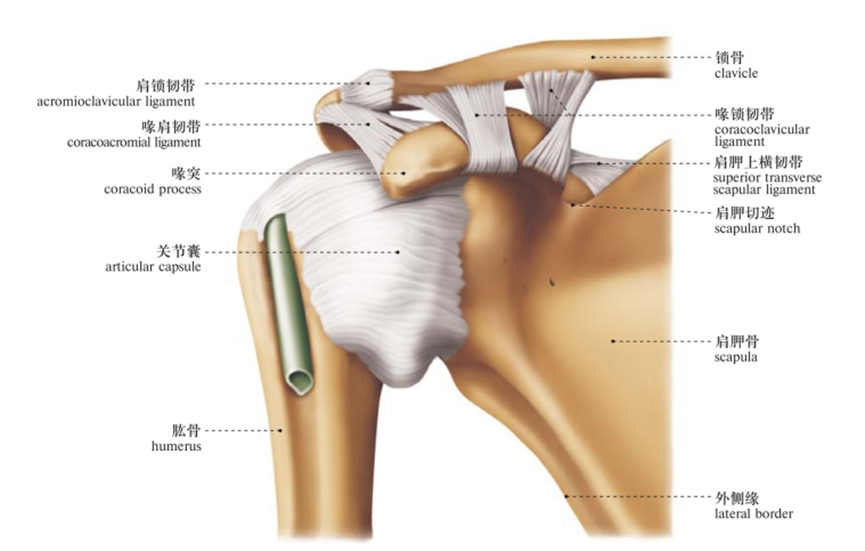

图1/2 肩关节韧带(前面观)

由肩胛骨的关节盂与股骨头组成,又叫肩肱关节(盂肱关节)。是典型的多轴球窝关节,为全身最灵活的关节,可作三轴运动,即冠状轴上的屈和伸,矢状轴上的收和展,垂直轴上的旋内、旋外及环转运动。

因肱骨头较大,呈球形,关节盂浅而小,仅包绕肱骨头的1/3,关节囊薄而松弛,所以是人体运动范围最大而又最灵活的关节。

囊外:喙肱韧带、喙肩韧带及肌腱加强其稳定性。

1.喙肱韧带:

自喙突至肱骨大结节,部分纤维在后上部与关节囊融合,增强关节囊上部,防止肱骨头向上脱位。

2.盂肱韧带:

位于关节囊前壁,可分为上、中、下三部,自关节盂周缘前部至肱骨小结节。有加强关节囊前壁的作用。

3.肱骨横韧带:

为肱骨的固有韧带,横跨结节间沟的上方,有固定肱二头肌长头腱于结节间沟的作用。